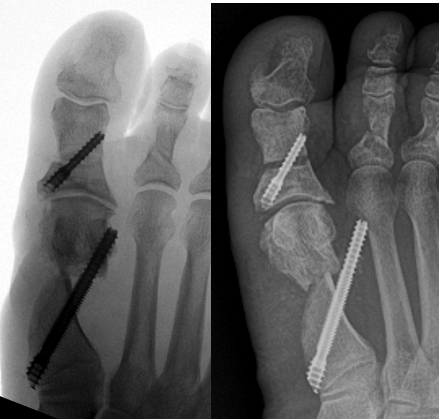

In Figures 2 A, B, C one can see an example of a nonunion at 1 year that required revision surgery. The patient used a bone stimulator for 6 months, and ultimately went on to revision surgery at 13 months postoperative from the index MIS bunion surgery. This was an example of a successful revision surgery, removing the initial hardware, utilizing an autogenous tricortical bone graft from the calcaneus, and a dual plating construct.

In Figures 3 A, B, C, D, the images depict the case of an elderly female who previously underwent a MIS bunion surgery. Unfortunately, she experienced a recurrent HAV and painful proximal hardware medially (Figures 3 A, B). She subsequently underwent hardware removal and revisional MIS bunion surgery (Figure 3 C, D).